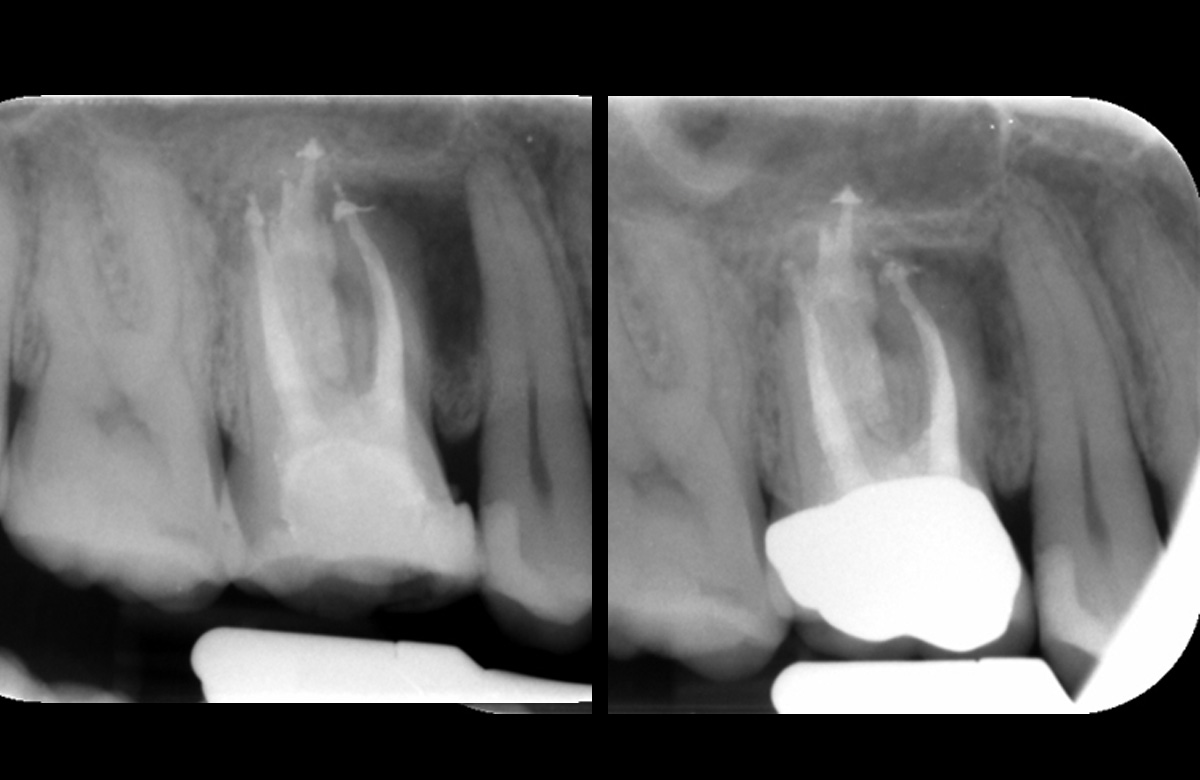

Pre obturation periapical radiograph of the tooth 16, checking cone length

Post obturation periapical radiograph showing obturation to length; right image: Review periapical radiograph showing increased bone infill around the mesiobuccal root

| PA demonstrates | Increased bone infill in comparison to post obturation PA taken 6 months prior |

| Obturation | With GP & AH Plus sealer. Warm vertical condensation technique. |

| Orifice barrier | GIC |

| Review | Healing in progress |

| Patient reports | The tooth has been feeling good since treatment was completed. I can eat on that side again. |